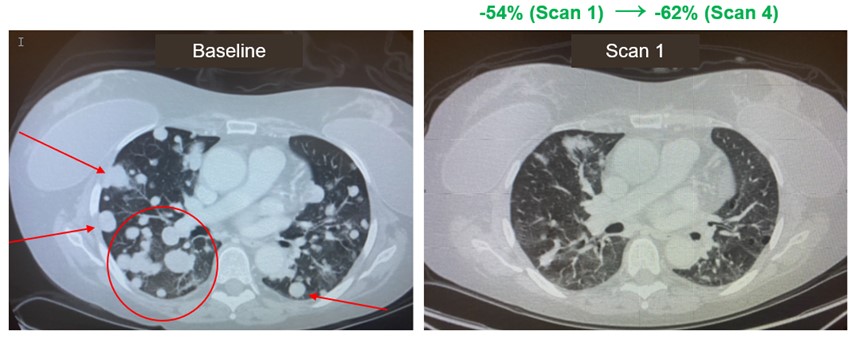

Notably, one RCC patient who achieved a response after treatment with amezalpat and nivolumab had previously been treated with nivolumab in combination with ipilimumab without experiencing an objective response and progressed on treatment, followed by further progression of cancer on both cabozantinib and everolimus. The initial RECIST PR was seen at the first on-study assessment at eight weeks and included a response in all target lesions as well as complete radiographic resolution of multiple sites of metastatic disease (see CT scan below) and has been confirmed at subsequent assessments beyond 12 months.

Partial Response in Late-Line RCC Patient Treated with amezalpat

and Nivolumab Combination Therapy